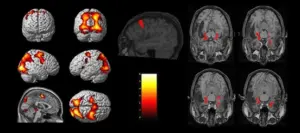

دومین دوره آموزشی تصویربرداری و آنالیز داده های تصویربرداری تشدید مغناطیسی عملکردی (fMRI)

-مبانی تصویربرداری و مقدمه ای بر آنالیز تصاویر fMRI

- تصویربرداری کارکردی تشدید مغناطیسی وابسته به Task و در حال استراحت

- کنتراست BOLD و منشا فیزیولوژیکی آن

- کاربردهای fMRI در Presurgical Planning و سایر کاربردهای آن

Functional MRI (fMRI)

-اصول پردازش تصاویر fMRI

- آشنایی با اصول پایه ای تصویربرداری fMRI

- روشهای پیشپردازش و پردازش دادههای fMIR

Functional MRI (fMRI) of the brain

Functional magnetic resonance imaging (fMRI)

-پردازش تصاویر fMRI (کار با نرم افزار)